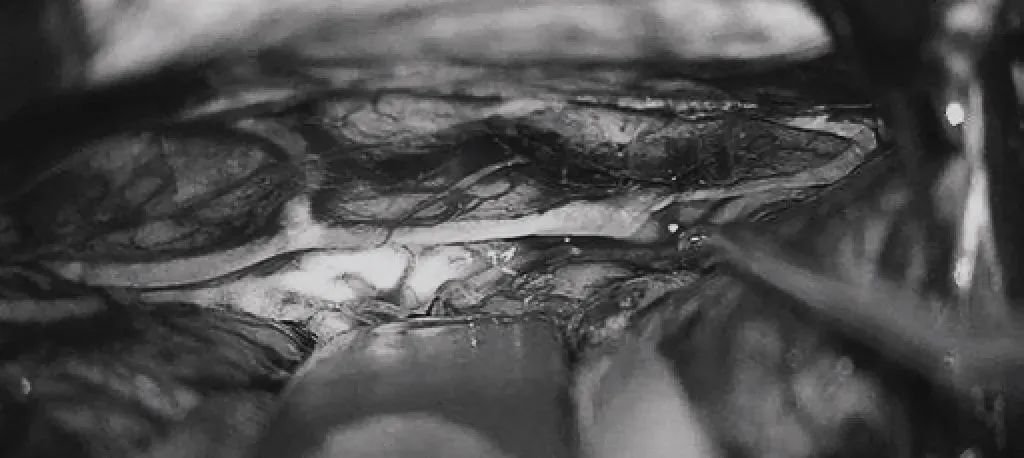

▼双额开颅,打开纵裂(鼻朝右,中线水平位,重力牵拉右侧半球),显露胼胝体、CmaA和PcaA。切开胼胝体2.5cm,显露透明隔内的AVM,大致显露ACA。

▼将AVM后缘向前牵离穹窿。

▼在透明隔底部保留FoM、穹窿和右侧SepV。